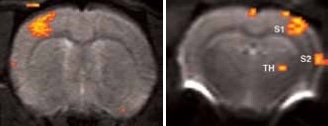

BOLD activation at 11.7 Tesla using the quadrature surface coil with a resolution of (left) 300 x 300 x 2000 μm3 for high quality and (right) 150 x 200 x 2000 μm3 for high sensitivity.

Figure 2. BOLD activation at 11.7 Tesla using the quadrature surface coil with a resolution of (left) 300 x 300 x 2000 μm3 for high quality and (right) 150 x 200 x 2000 μm3 for high sensitivity. Image Credit: Bruker BioSpin Group

Using older DBX electronics and linear surface coils at 7.0 Tesla, BOLD contrast with 400 x 400 x 2000 μm3 resolution can be obtained. Combined with T2-maps, loss of functional activity and its instant recovery as well as stroke lesion (Figure 1) was defined[4,5]. A combination of faster AVANCE II readout electronics, quadrature surface coil, and higher field strength of 11.7 Tesla increased both resolution and SNR to less than 200 x 200 x 2000 μm3, which is more than sufficient to identify the tiny structures along the neuronal activity pathway like the thalamus and secondary somatosensory cortex S2 (Figure 2) with BOLD contrast.